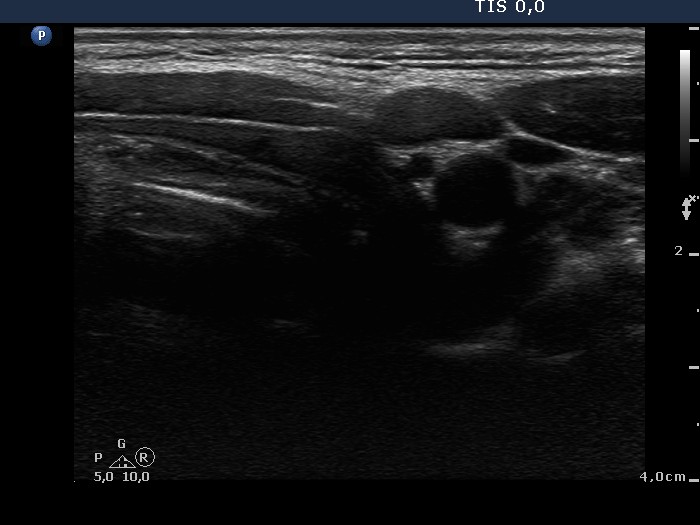

Ultrasonography: The thyroid was echonormal with a small insignificant moderately hypoechogenic lesion in the right lobe. There was a hypoechogenic nodule in the left lobe. The nodule contained numerous microcalcifications and coarse calcification, as well. The intranodular blood flow was a little bit increased. We found an enlarged lymph node in the left side of the neck.